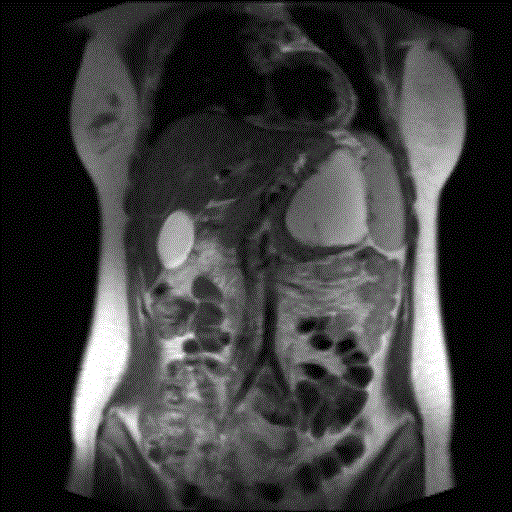

Figure 2. T2-weighted coronal MR image showed a simple cystic mass of the pancreatic tail displacing laterally the spleen; the thin line of hypointensity due to internal septum is clearly detected.